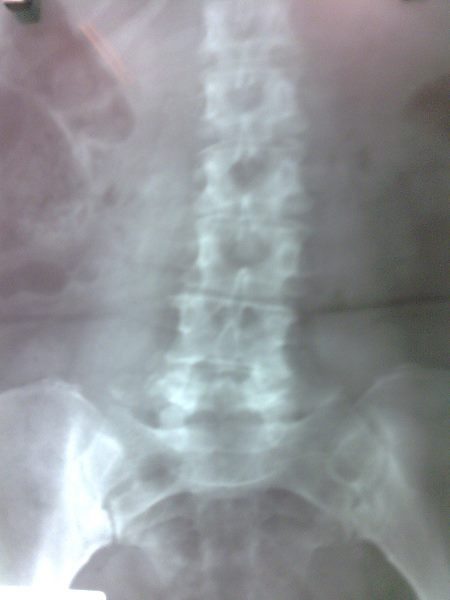

Radiografías con enfoque en fisiatría

Envíado por Dr. Hernán Darío Sánchez Ramos